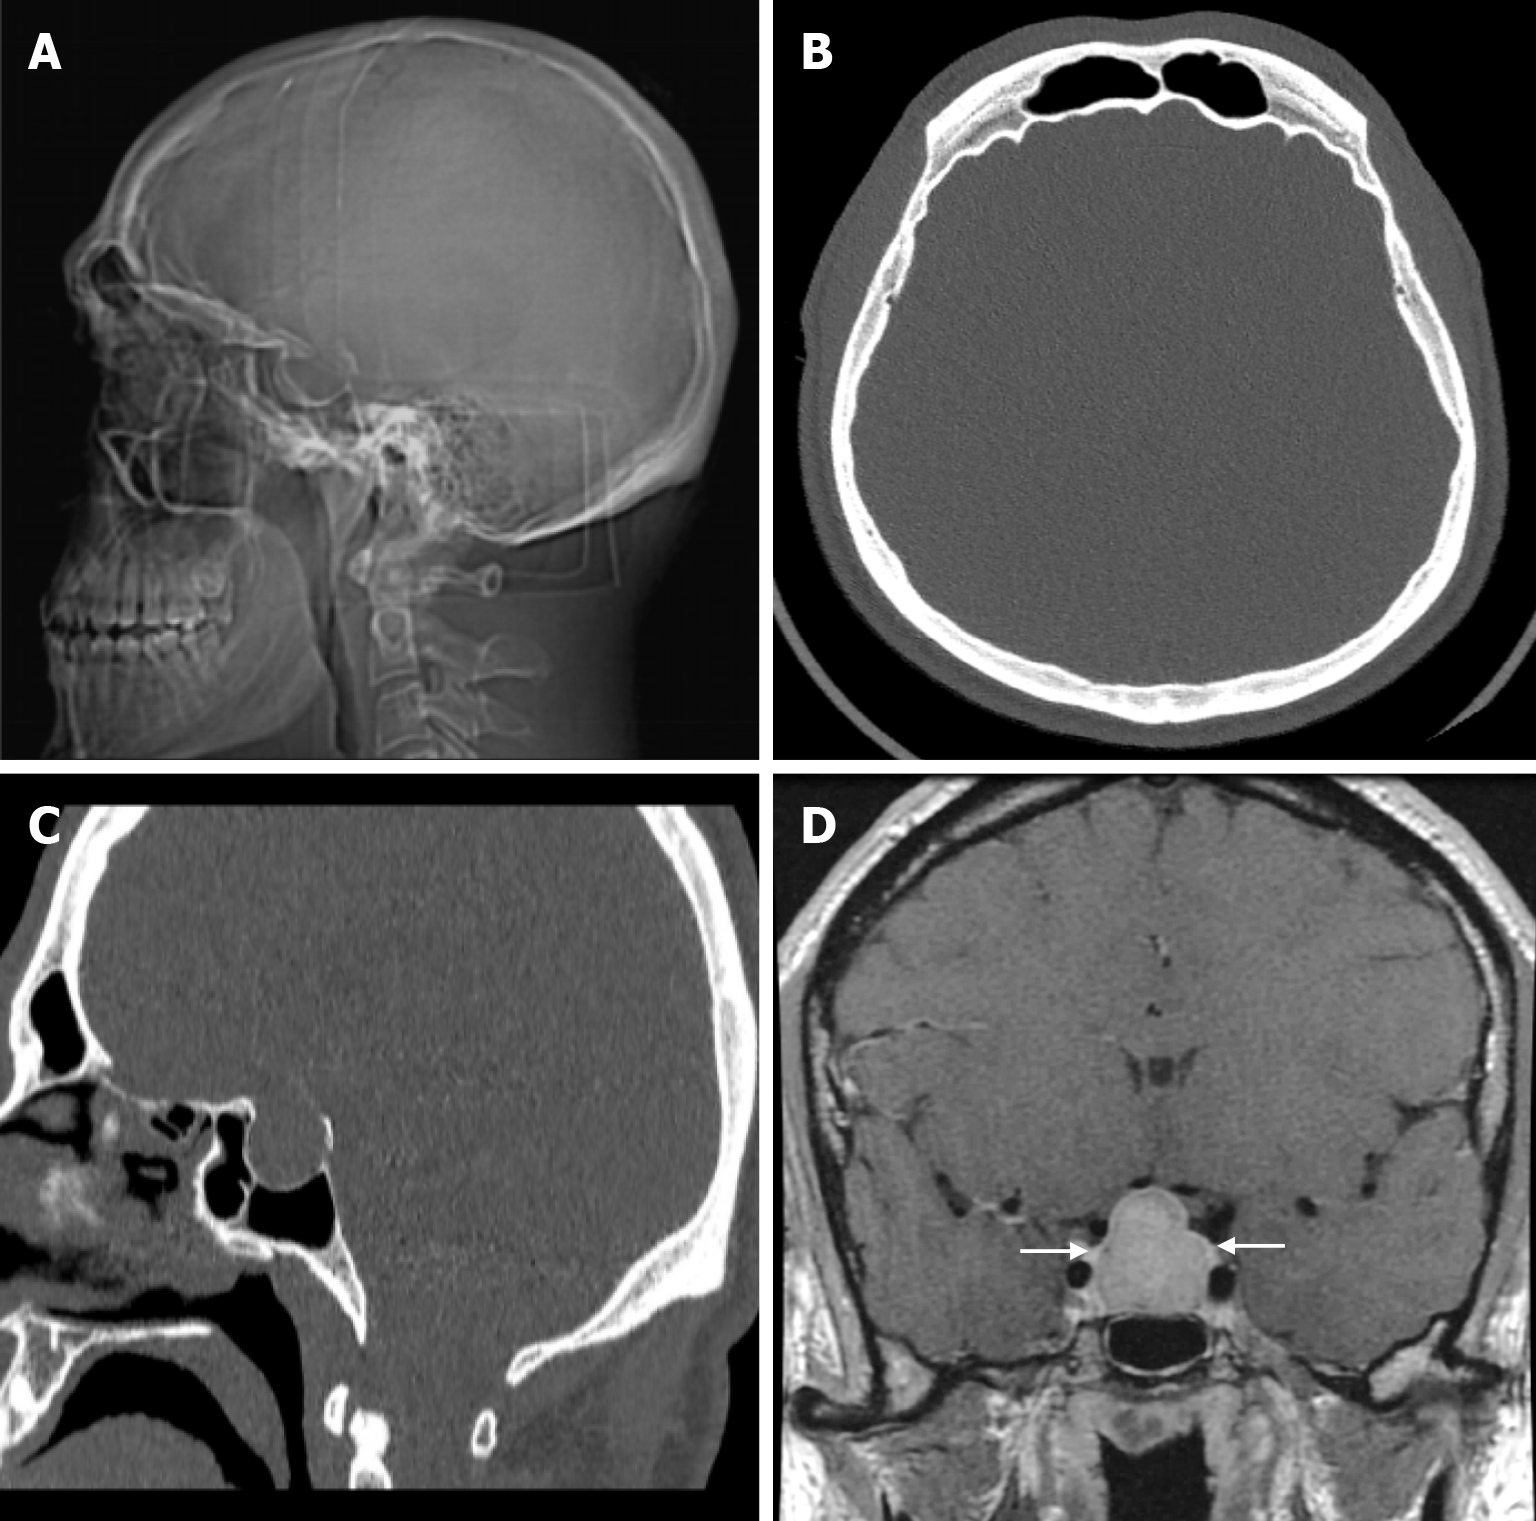

Acromegaly is a rare metabolic disorder that develops insidiously. It is characterised by chronically elevated levels of growth hormone and insulin-like growth factor 1 in the blood, which can lead to high morbidity and mortality. The average delay from onset of symptoms to diagnosis is estimated to be 7-10 years. The effects of growth hormone on the skeleton vary. This depends on the degree of skeletal maturity. Excessive secretion of growth hormone causes gigantism when the growth plates are still open and periosteal reactions with bone growth when the growth plates are closed. Radiographic enlargement of the sella turcica is due to the direct effect of the pituitary tumor (Figure 16). Other skull abnormalities result from the effects of excessive periosteal bone formation and include prominence of the occipital protuberance, cortical thickening of the calvarium, widening of the maxillary and frontal sinuses, enlargement and elongation of the mandible, increased mandibular angle and formation of a supraorbital crest. These changes result in a clinically significant prominence of the forehead[57].

Meningiomas account for about 20% of all primary intracranial tumors and are the most common benign tumors. Primary extradural meningiomas are a rare subtype of meningioma, accounting for less than 2% of all meningiomas. Primary intraosseous meningiomas occur within the bone, particularly in the calvarium, and account for two-thirds of all primary extradural meningiomas. The frontoparietal and orbital regions are the most common sites for primary intraosseous meningiomas. The incidence is slightly higher in women and has a bimodal distribution, peaking between the second decade of life and the ages of 50 and 70. The most common presentation of primary intraosseous meningioma of calvarial origin is a slowly growing asymptomatic mass. Headache is the second most common symptom reported. The patho

Primary intraosseous meningioma is typically seen on CT as a sclerotic lesion with bone expansion, hyperostosis, and contour irregularities in the inner and/or outer table (Figure 21). On MRI, the tumor has a low signal on T1-weighted images and variable signal intensity on T2-weighted images, and contrast enhancement is not expected. The dural tail, which can be seen in intradural meningiomas, is not expected in intraosseous meningiomas. However, if it has caused a defect in the dura or an invasion, contrast enhancement may be seen in the dura[49,64]. Proton magnetic resonance spectroscopy (MRS) of the soft tissue component may characteristically show alanine (Ala, 1.47 ppm doublet inversion at long echo times). T2* dynamic susceptibility contrast-perfusion-weighted imaging (DSC-PWI) time-intensity curves (TIC) of the soft tissue component of primary intraosseous meningioma typically show a curve with little or no return from the baseline. These tumors characteristically have very high relative cerebral blood volume (rCBV) values[8].